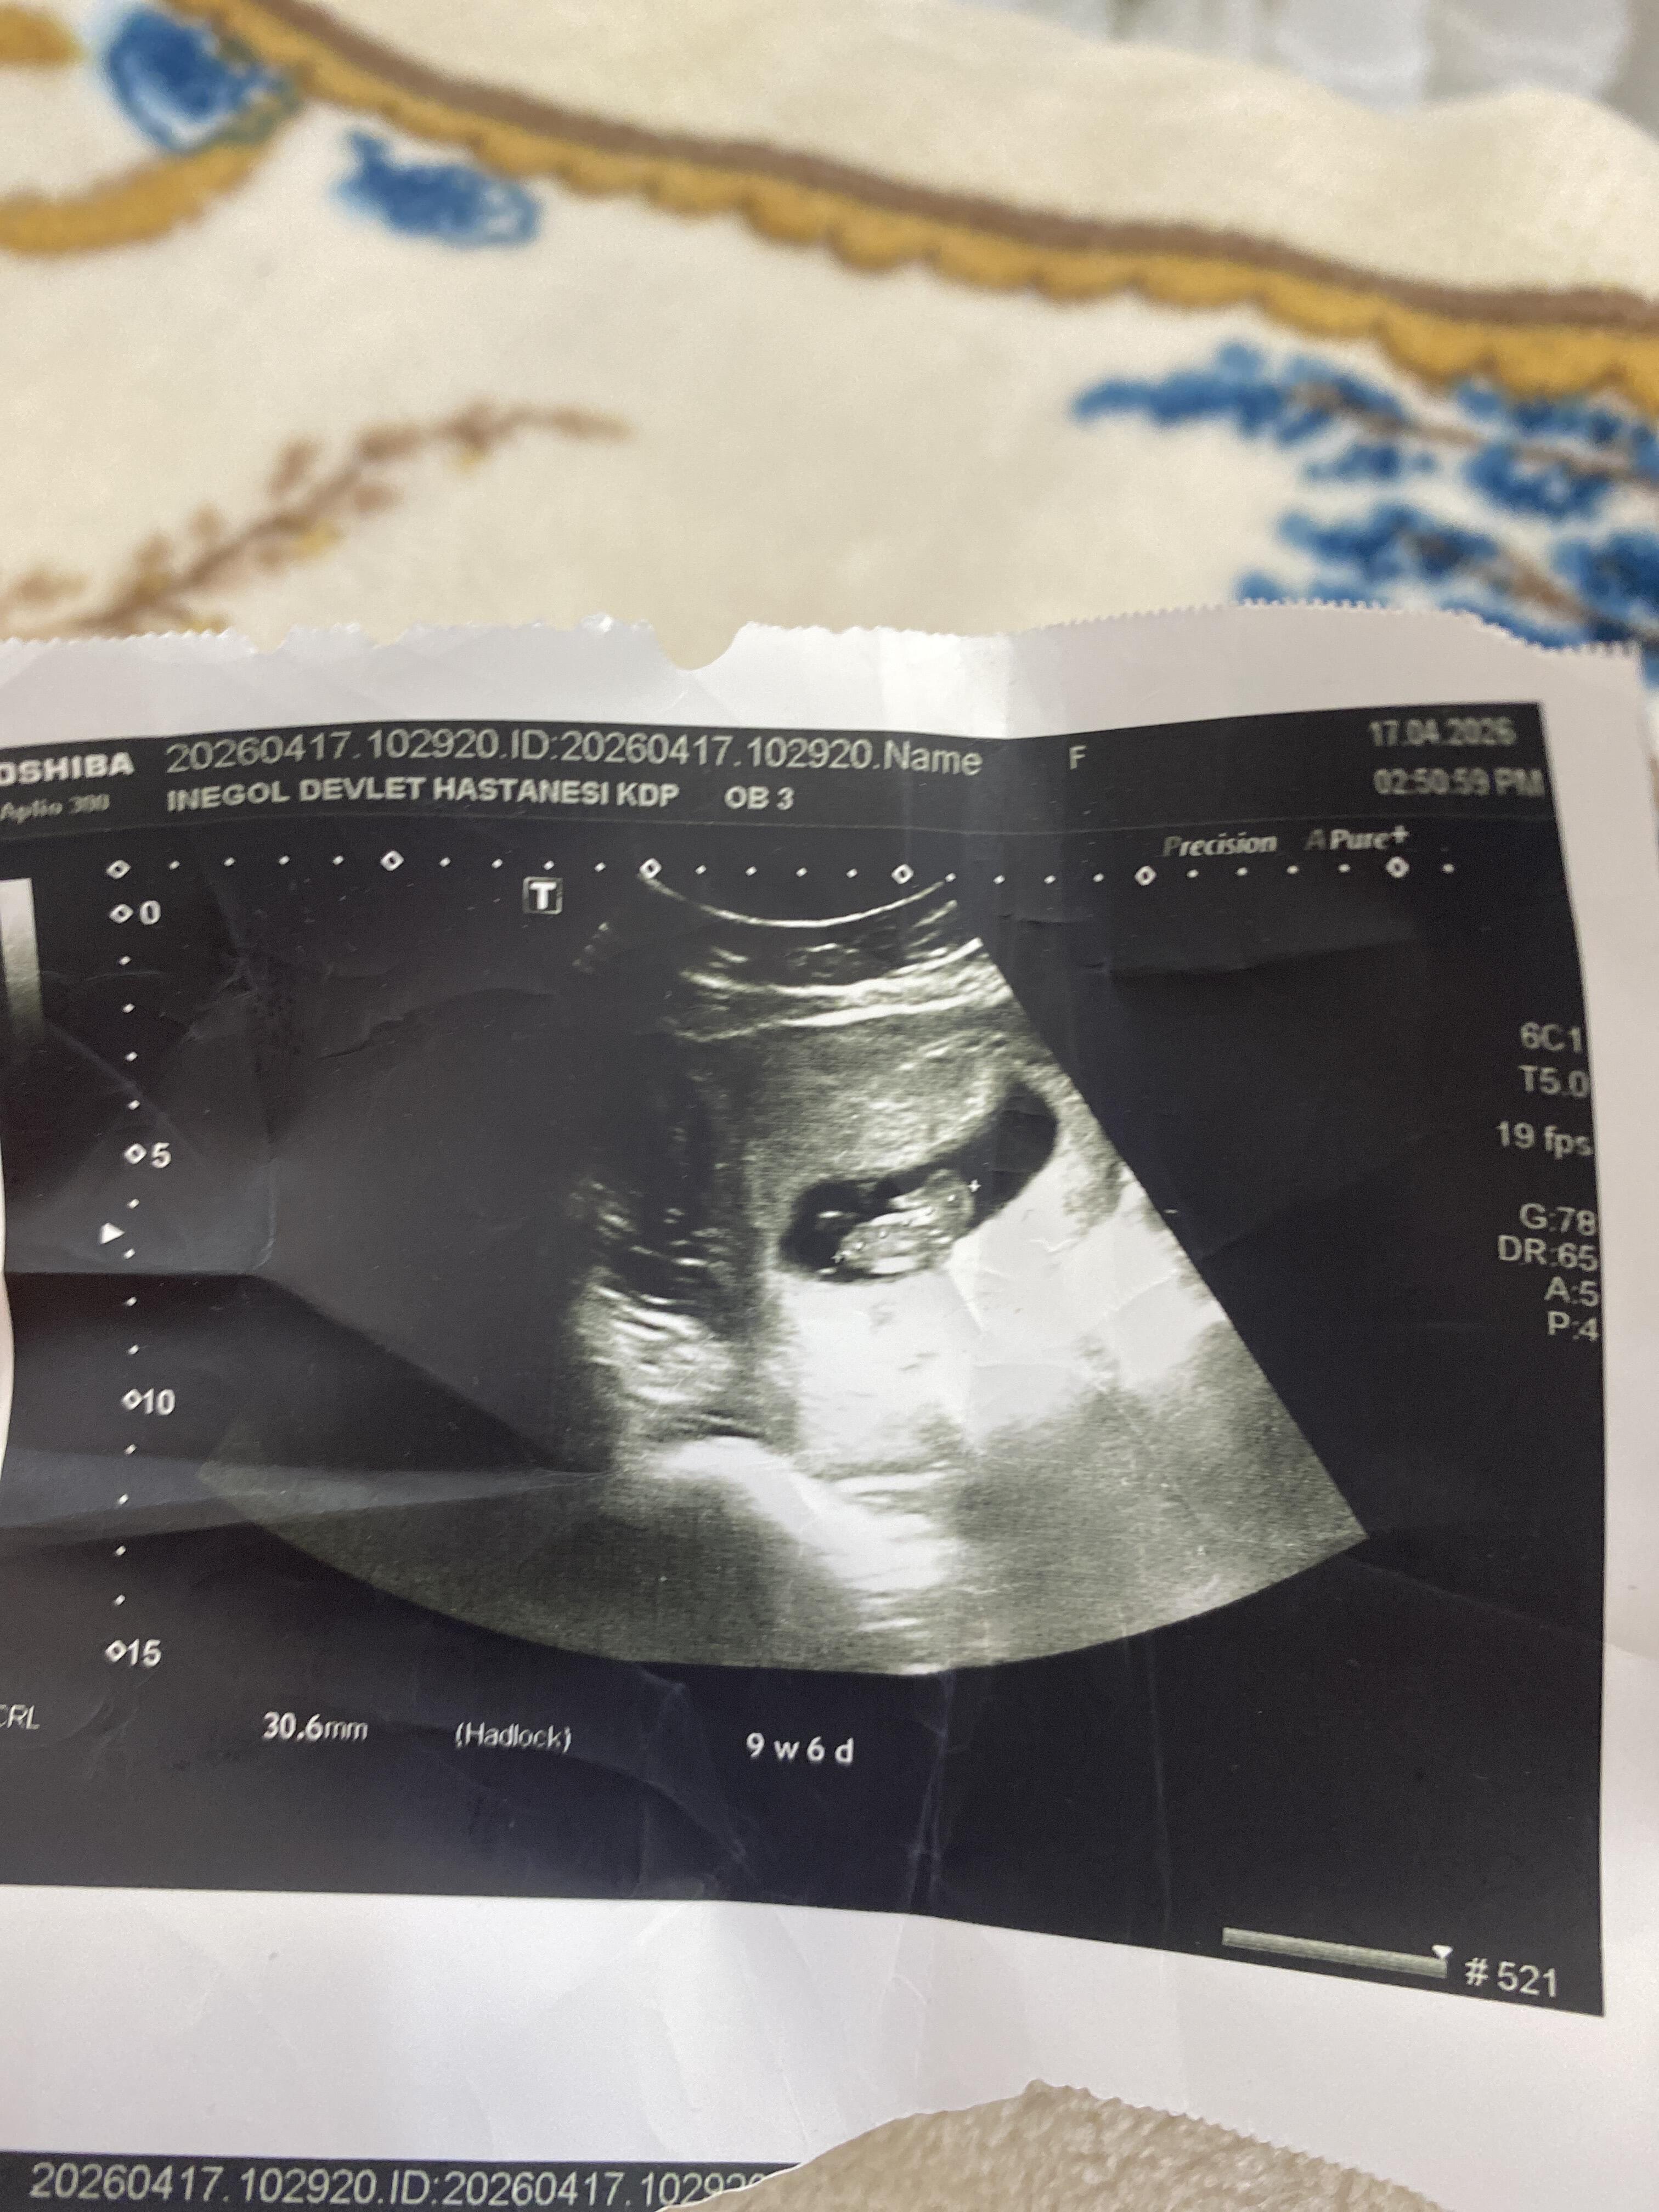

Erken hafta cinsiyetten anlayanlar ❣️

9 hafta 6 günlük eğlenceli tahminlerinizi bekliyorum